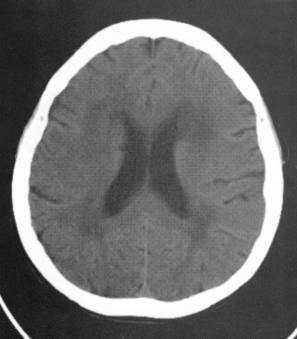

脑白质脱髓鞘

脑白质脱髓鞘改变